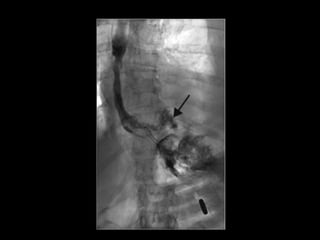

• #63 Ösophagus-Monokontrast mit wasserlöslichem Kontrastmittel (100 ml Peritrast®). Kontrastmittelaustritt im distalen Ösophagus links dorsolateral in die Pleurahöhle ( Pfeil )